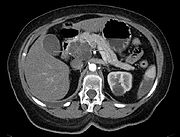

تُستخدم تقنيات التصوير الطبي، مثل التصوير المقطعي المحوسب والتنظير بالموجات فوق الصوتية لتأكيد التشخيص وللمساعدة في تحديد ما إذا كان يمكن إزالة الورم جراحيًا ("قابلية الاستئصال").[12] في تباين التصوير الطبقي المحوسب، يظهر سرطان البنكرياس عادةً زيادة تدريجية في امتصاص الأشعة، بدلاً من الانجراف السريع كما يظهر في البنكرياس الطبيعي أو الاغتسال المتأخر كما يظهر في التهاب البنكرياس المزمن.[29] يمكن أيضًا استخدام التصوير بالرنين المغناطيسي والتصوير المقطعي بالإصدار البوزيتروني،[2] وقد يكون تصوير الپنكرياس والقنوات الصفراوية بالرنين المغناطيسي مفيدًا في بعض الحالات.[22] الموجات فوق الصوتية على البطن أقل حساسية ولا تظهر الأورام الصغيرة، ولكن يمكنها تحديد السرطانات التي انتشرت في الكبد وتراكم السوائل في التجويف البريتوني (الاستسقاء).[12] يمكن استخدامها لإجراء فحص أولي سريع ورخيص قبل التقنيات الأخرى.[30]